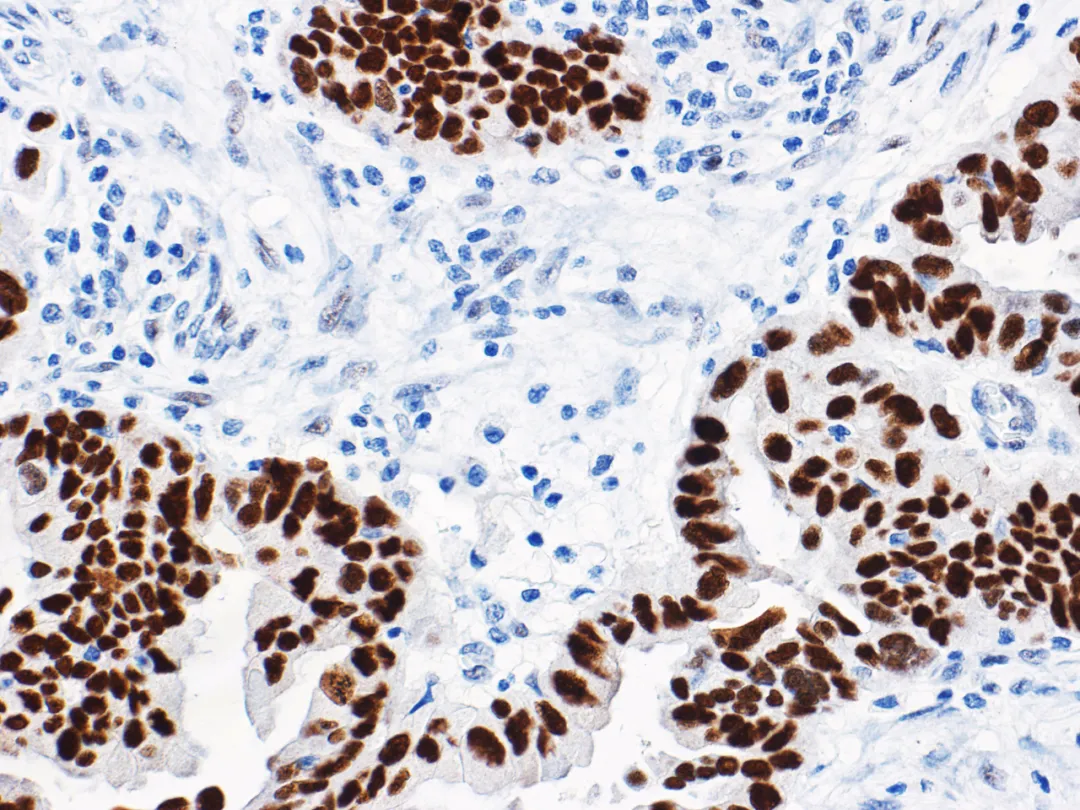

p53 immunohistochemistry helps differentiate ovarian high-grade serous carcinoma (as shown in Figure 1) from low-grade serous carcinoma (as shown in Figure 2). This diagnostic classification is significant for clinical treatment: regarding treatment plans, high-grade serous carcinoma (Tp53gene mutation) — p53 immunohistochemistry results are mostly abnormal expression states, requiring at least 6 cycles of platinum-based neoadjuvant therapy after surgery. Low-grade serous carcinoma (Tp53gene normal) — p53 shows wild-type expression, and neoadjuvant therapy of 3-6 cycles is administered only for stage Ic or above after surgery. High-grade serous carcinoma with BRCA1/2 mutations can be treated with relevant inhibitors, while low-grade serous carcinoma may be treated with hormone therapy; specific targeted therapy drugs also differ for serous carcinomas of different grades.

Figure 1. High-grade ovarian serous carcinoma – Mutant p53 nuclear overexpression